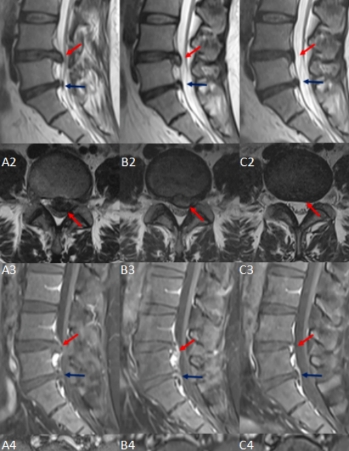

基于MRI的腰椎间盘突出物体积的计算!